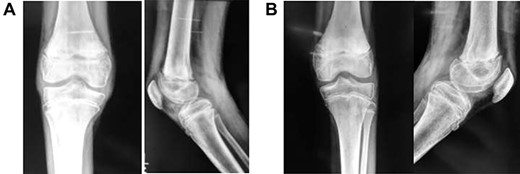

In theatre, general anaesthesia and prone positioning were performed. Closed reduction with gentle traction was achieved, followed by gradual flexion of the knee (Wilkin’s Manoeuvre). The physeal fragment was reduced with both thumbs, and reduction checked under mobile X-ray—good realignment was confirmed. Final fixation was achieved with percutaneous smooth K-wires in a cross construct (Figs 2, 3A and B). An anterior slab maintaining knee flexion was then applied. This process was repeated contralaterally. After 24 h and with adequate analgesia, bilateral foot-drop was noted. Bilateral posterior slabs were then applied.

Frontal view of both knees after closed reduction and K-wire fixation

(A) Lateral view of right knee after closed reduction, K-wire fixation and anterior slab application; (B) Lateral view of left knee after closed reduction, K-wire fixation and anterior slab application